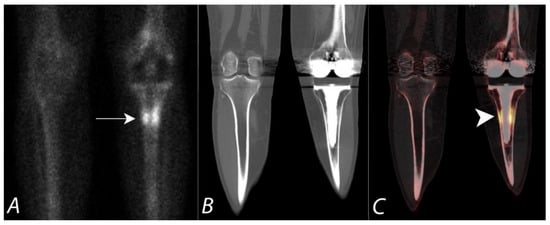

6. Hip Pain

7. Knee Pain